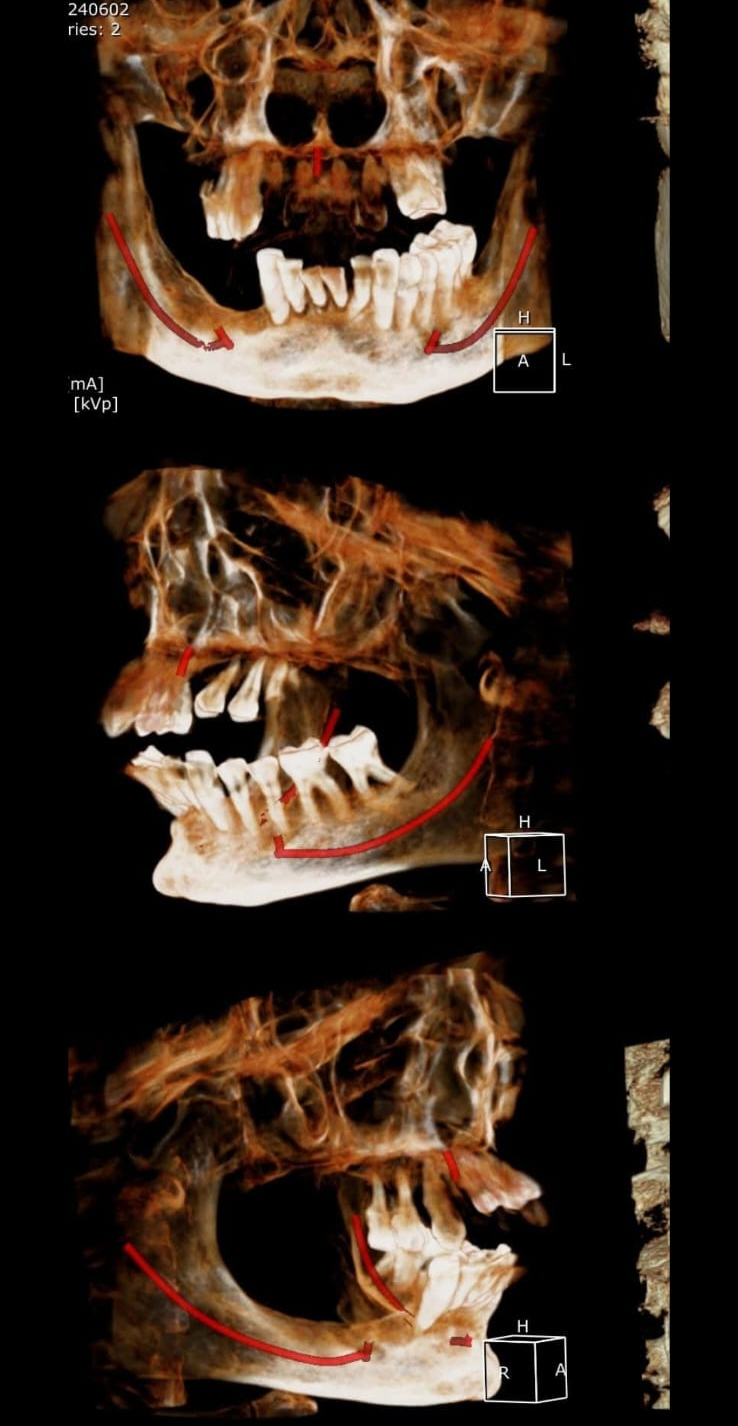

Full Mouth Implant Case

Full Mouth Implants with all Ceramic Crowns